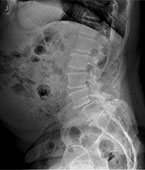

• Patient Cases Before picBefore

• Patient Reviews before image case 1Before Surgery